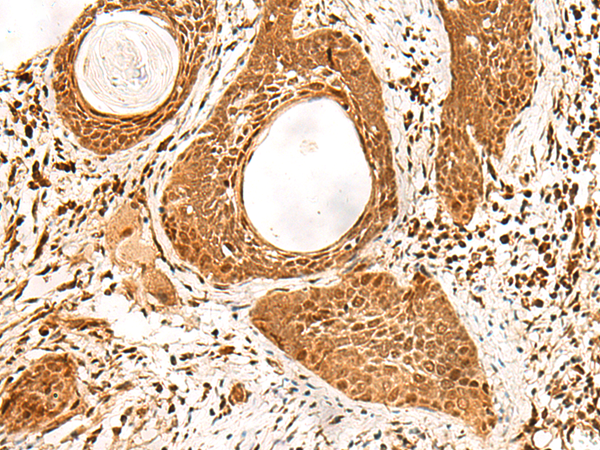

分类: 科研抗体货号: P09904别名: PSP1应用: IHC反应种属: Human, Mouse, Rat